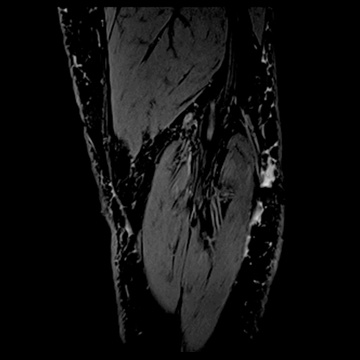

膝関節

PD 脂肪抑制

MRI画像例

左右にスクロールして画像をご覧いただけます。